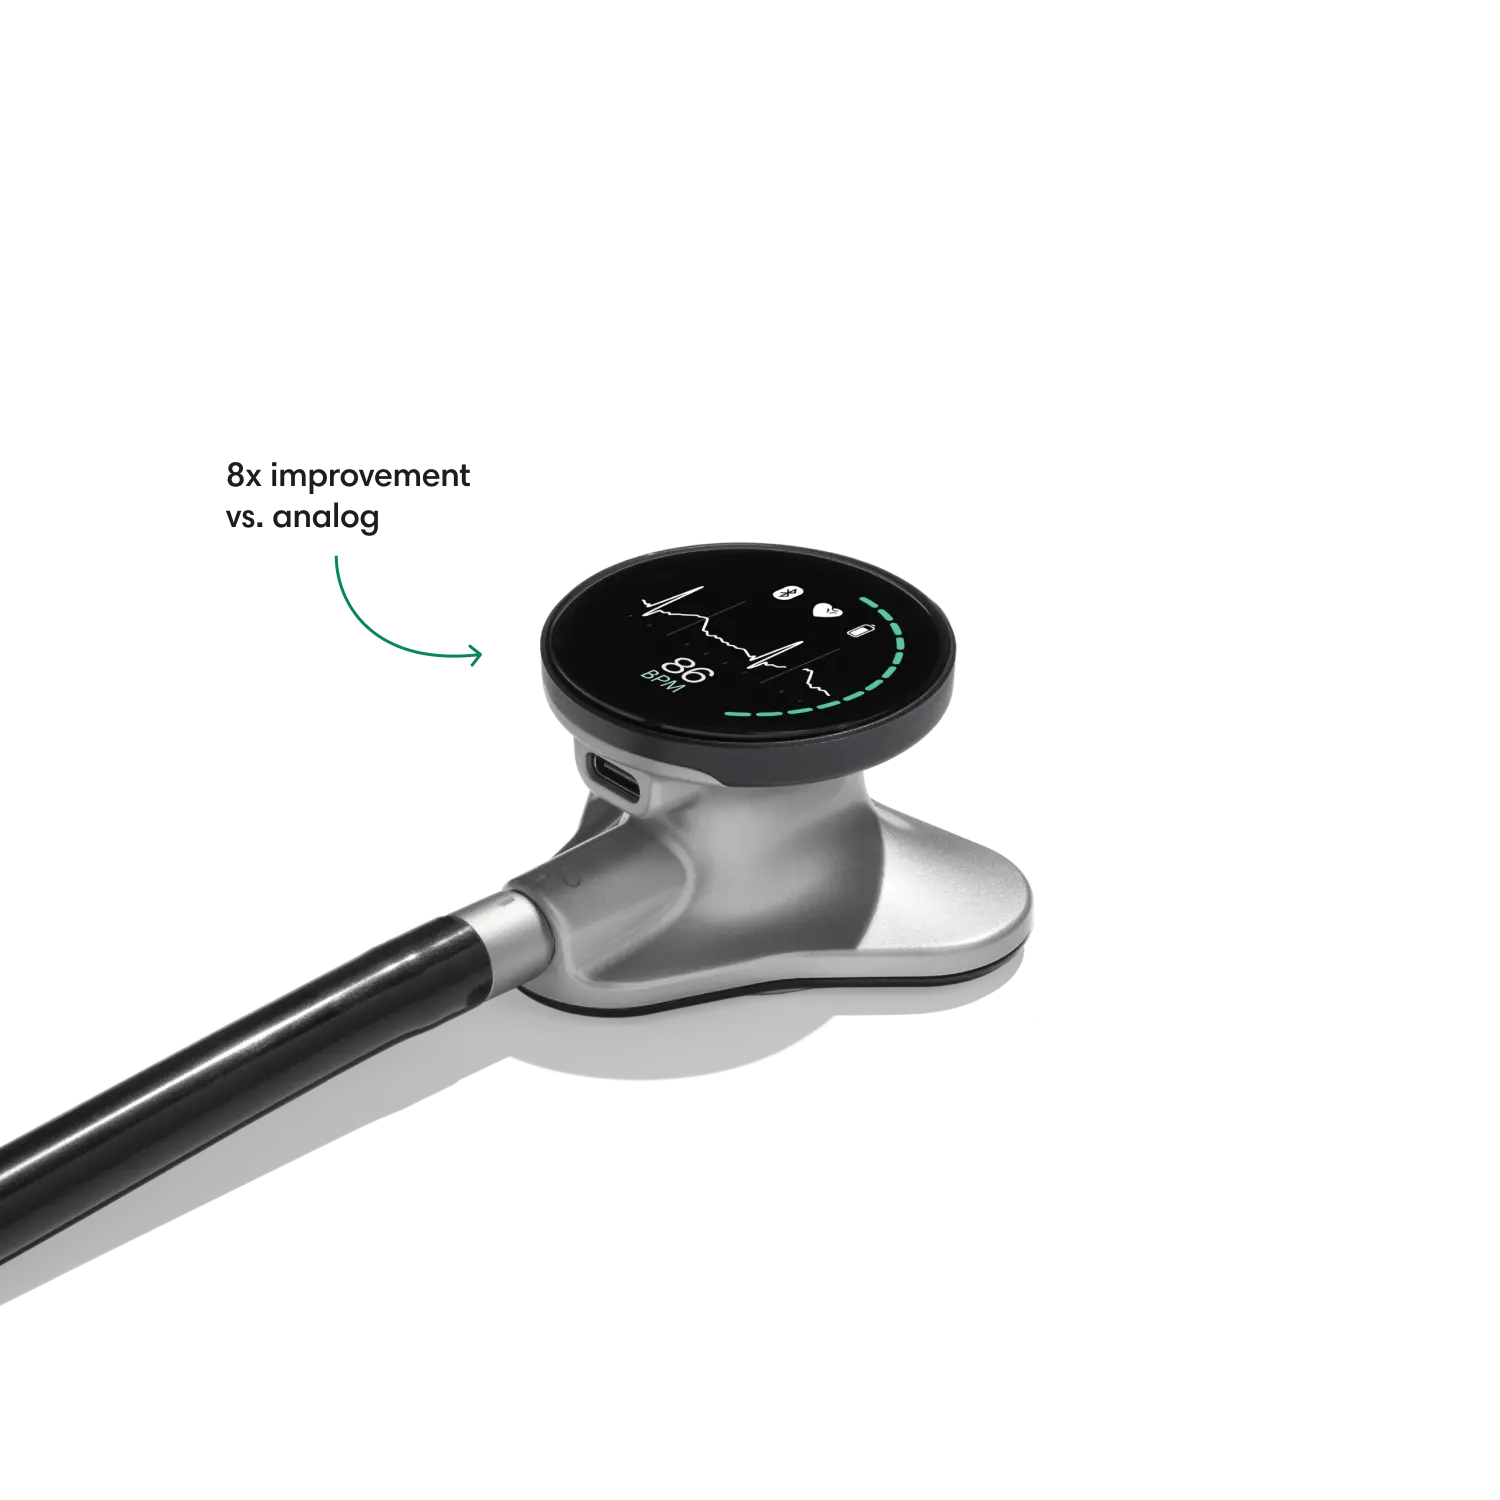

- Reduces background noise 8x better vs. a typical analog stethoscope.